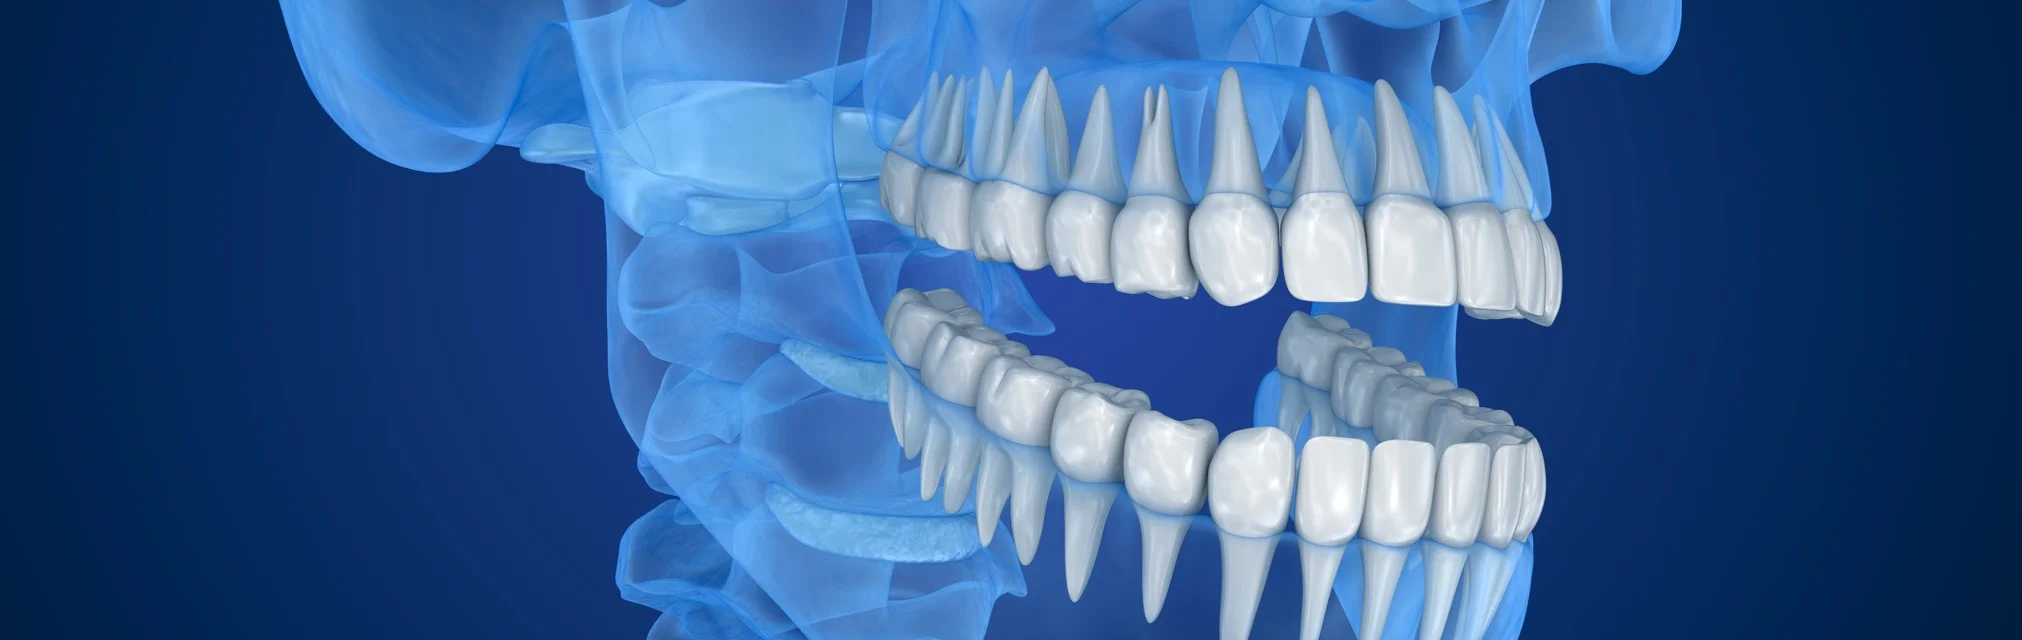

На смену 2D снимкам пришли КТ снимки (компьютерная томография], которые в обиходе называют 3D снимками —новый уровень диагностики.

3D снимки позволяют стоматологам рассмотреть зубы под разными углами.

Врач изучает 3D снимки на компьютере и в отличии от 2D снимков, он может крутить изображение под любым углом, который ему необходим, заглядывать «внутрь» каждого зуба.